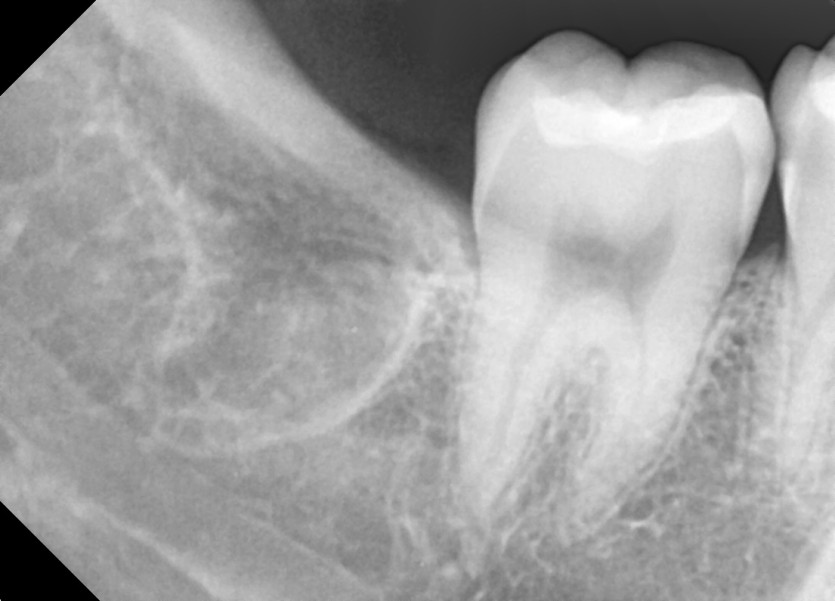

#18,48 사랑니 발치

구강 외과 전문의가 당일 발치했습니다.